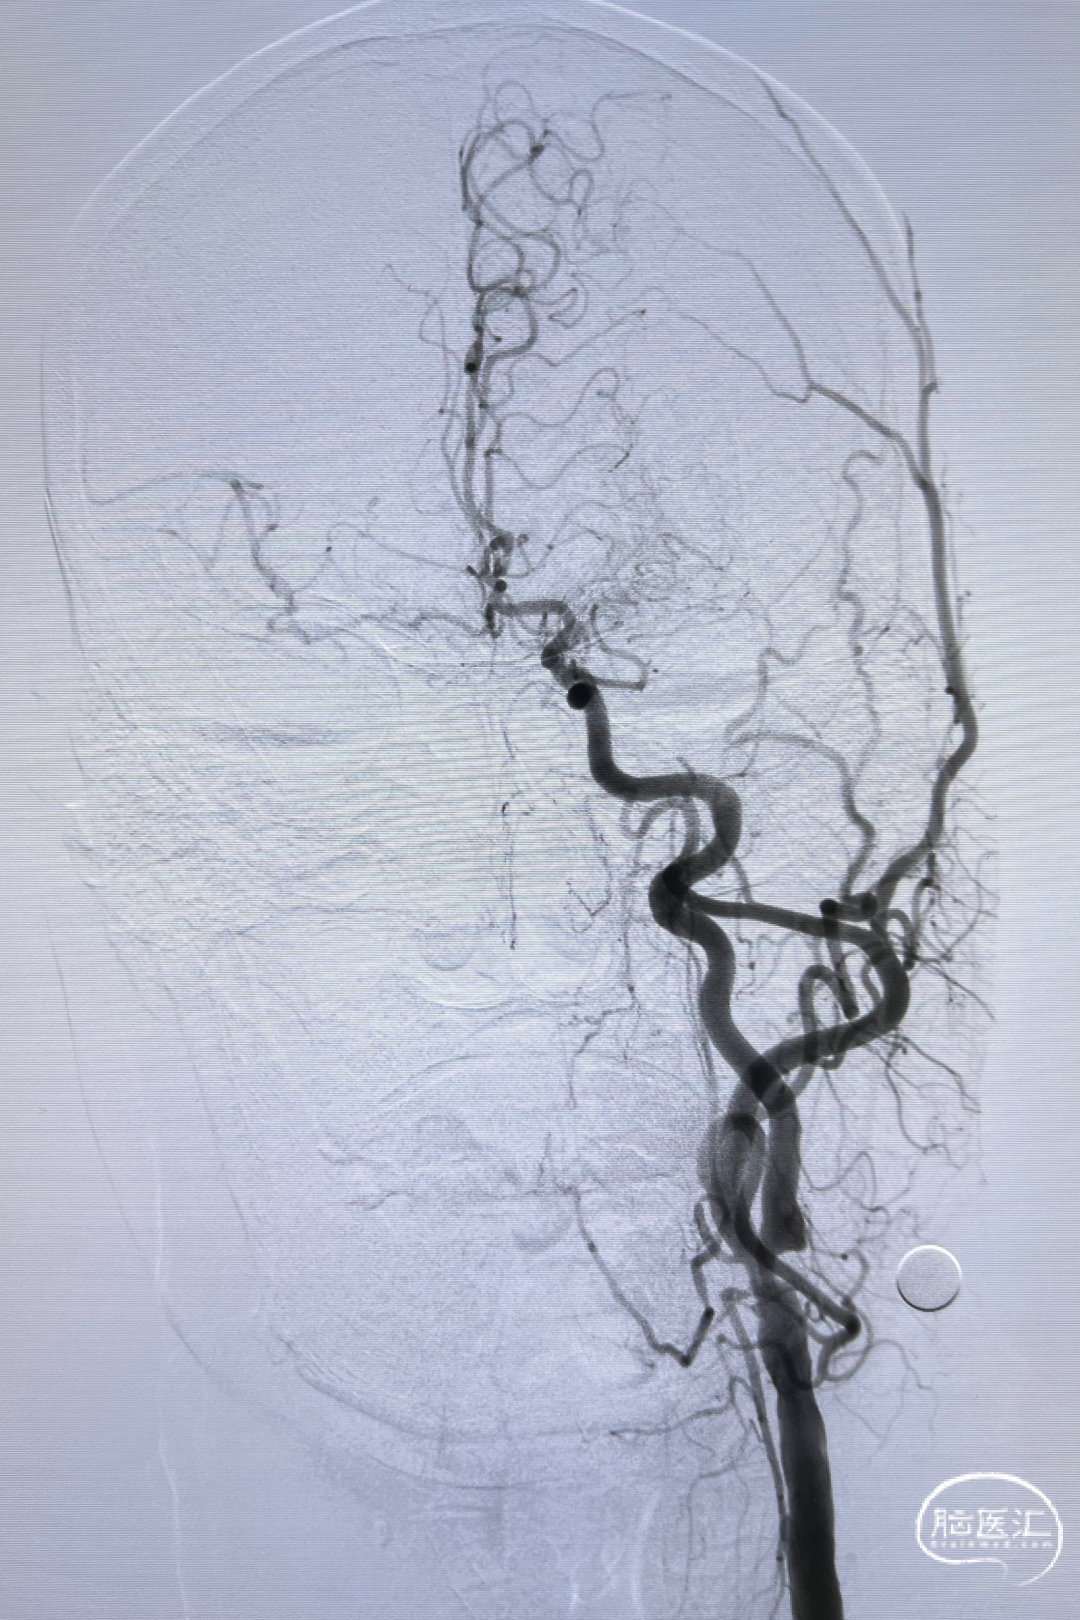

双侧股动脉造影:双侧髂动脉支架迂曲,不能通过造影导管及导丝。

经桡入路完成全脑血管造影:主动脉弓。

右侧颈内动脉闭塞。